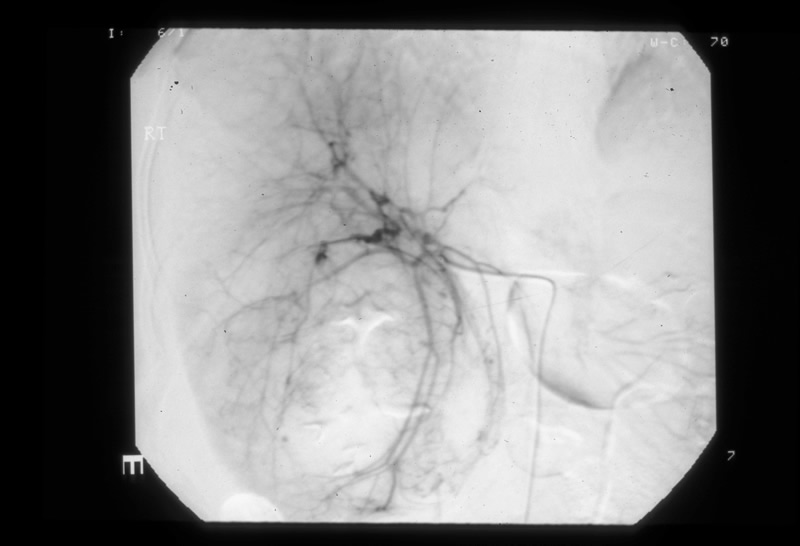

An angiogram showed that the branches of the right hepatic artery were splayed and attenuated within the right hemi-liver, particularly inferiorly. Selective angiography of the right hepatic artery showed that segments 7 and 8 were well filled but the vessels to segments 5 and 6 were poorly filled due to haematoma.

Selective embolisation of the right hepatic artery

Figure 2 - click image to enlarge